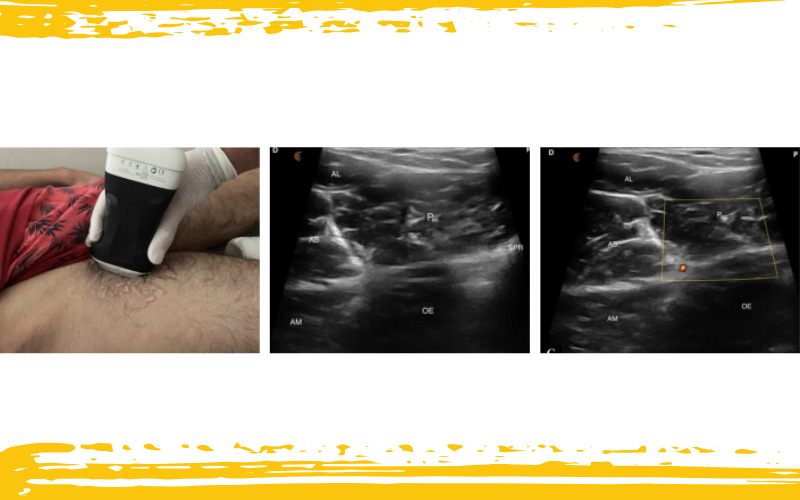

Desde ahí, se rota la sonda al plano longitudinal y se inclina hasta delinear completamente los bordes y cuerpo del músculo. Este paso es crucial, porque sólo con una visualización clara podemos avanzar al siguiente nivel.

Infografía 3. Visualización del músculo pectíneo en el plano longitudinal.

M – medial; L – lateral; P – proximal; D – distal; AL – músculo aductor largo;

AB – músculo aductor corto; AM – músculo aductor mayor; IP – músculo iliopsoas;

FN – nervio femoral; OE – músculo obturador externo; Pec – músculo pectíneo;

SPR – ramo púbico superior.